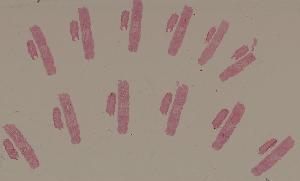

教学切片

高倍视野

低倍视野